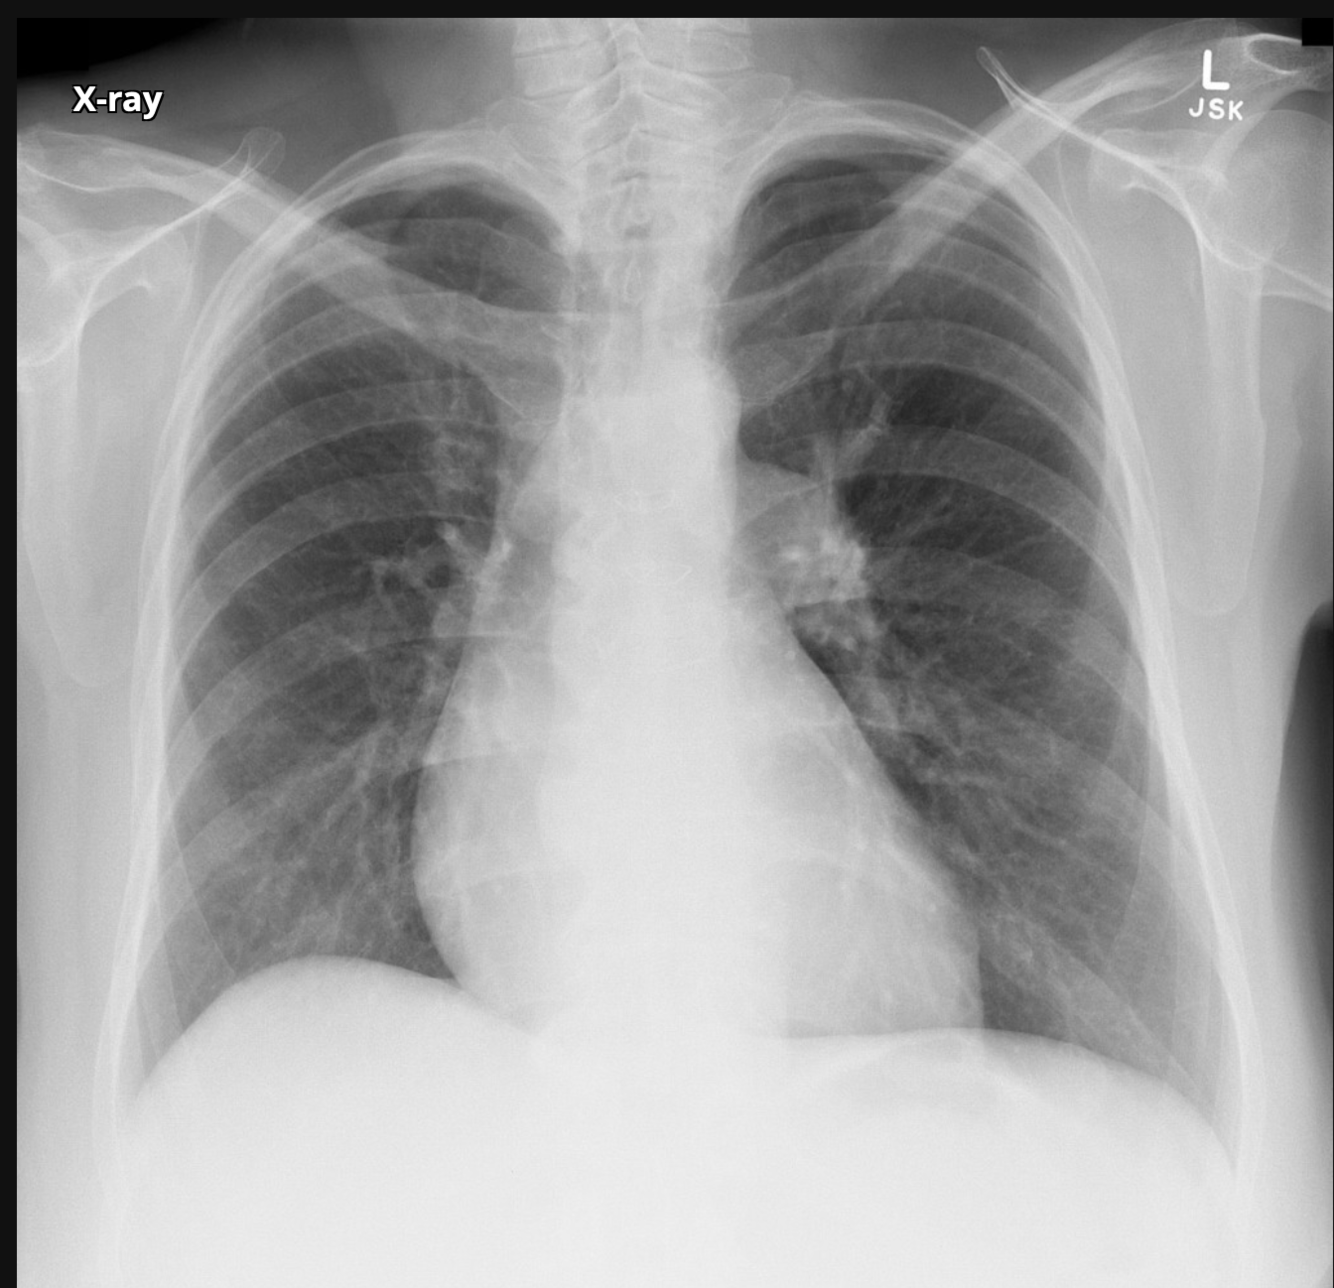

Pre cardiology workup for systolic murmur.

Patient Data

Age:60 years

Gender:Female

what is the dx?

what sign is demonstrated

Chen sign is described as the prominence of left basal pulmonary vasculature compared to the right base due to the asymmetric increase in pulmonary blood flow to the left lung. It is secondary to preferential blood flow into the left pulmonary artery after passing through the stenosed pulmonary valve during systole.

Enlargement of the left pulmonary artery is secondary to the same effect, causing post stenotic dilatation.